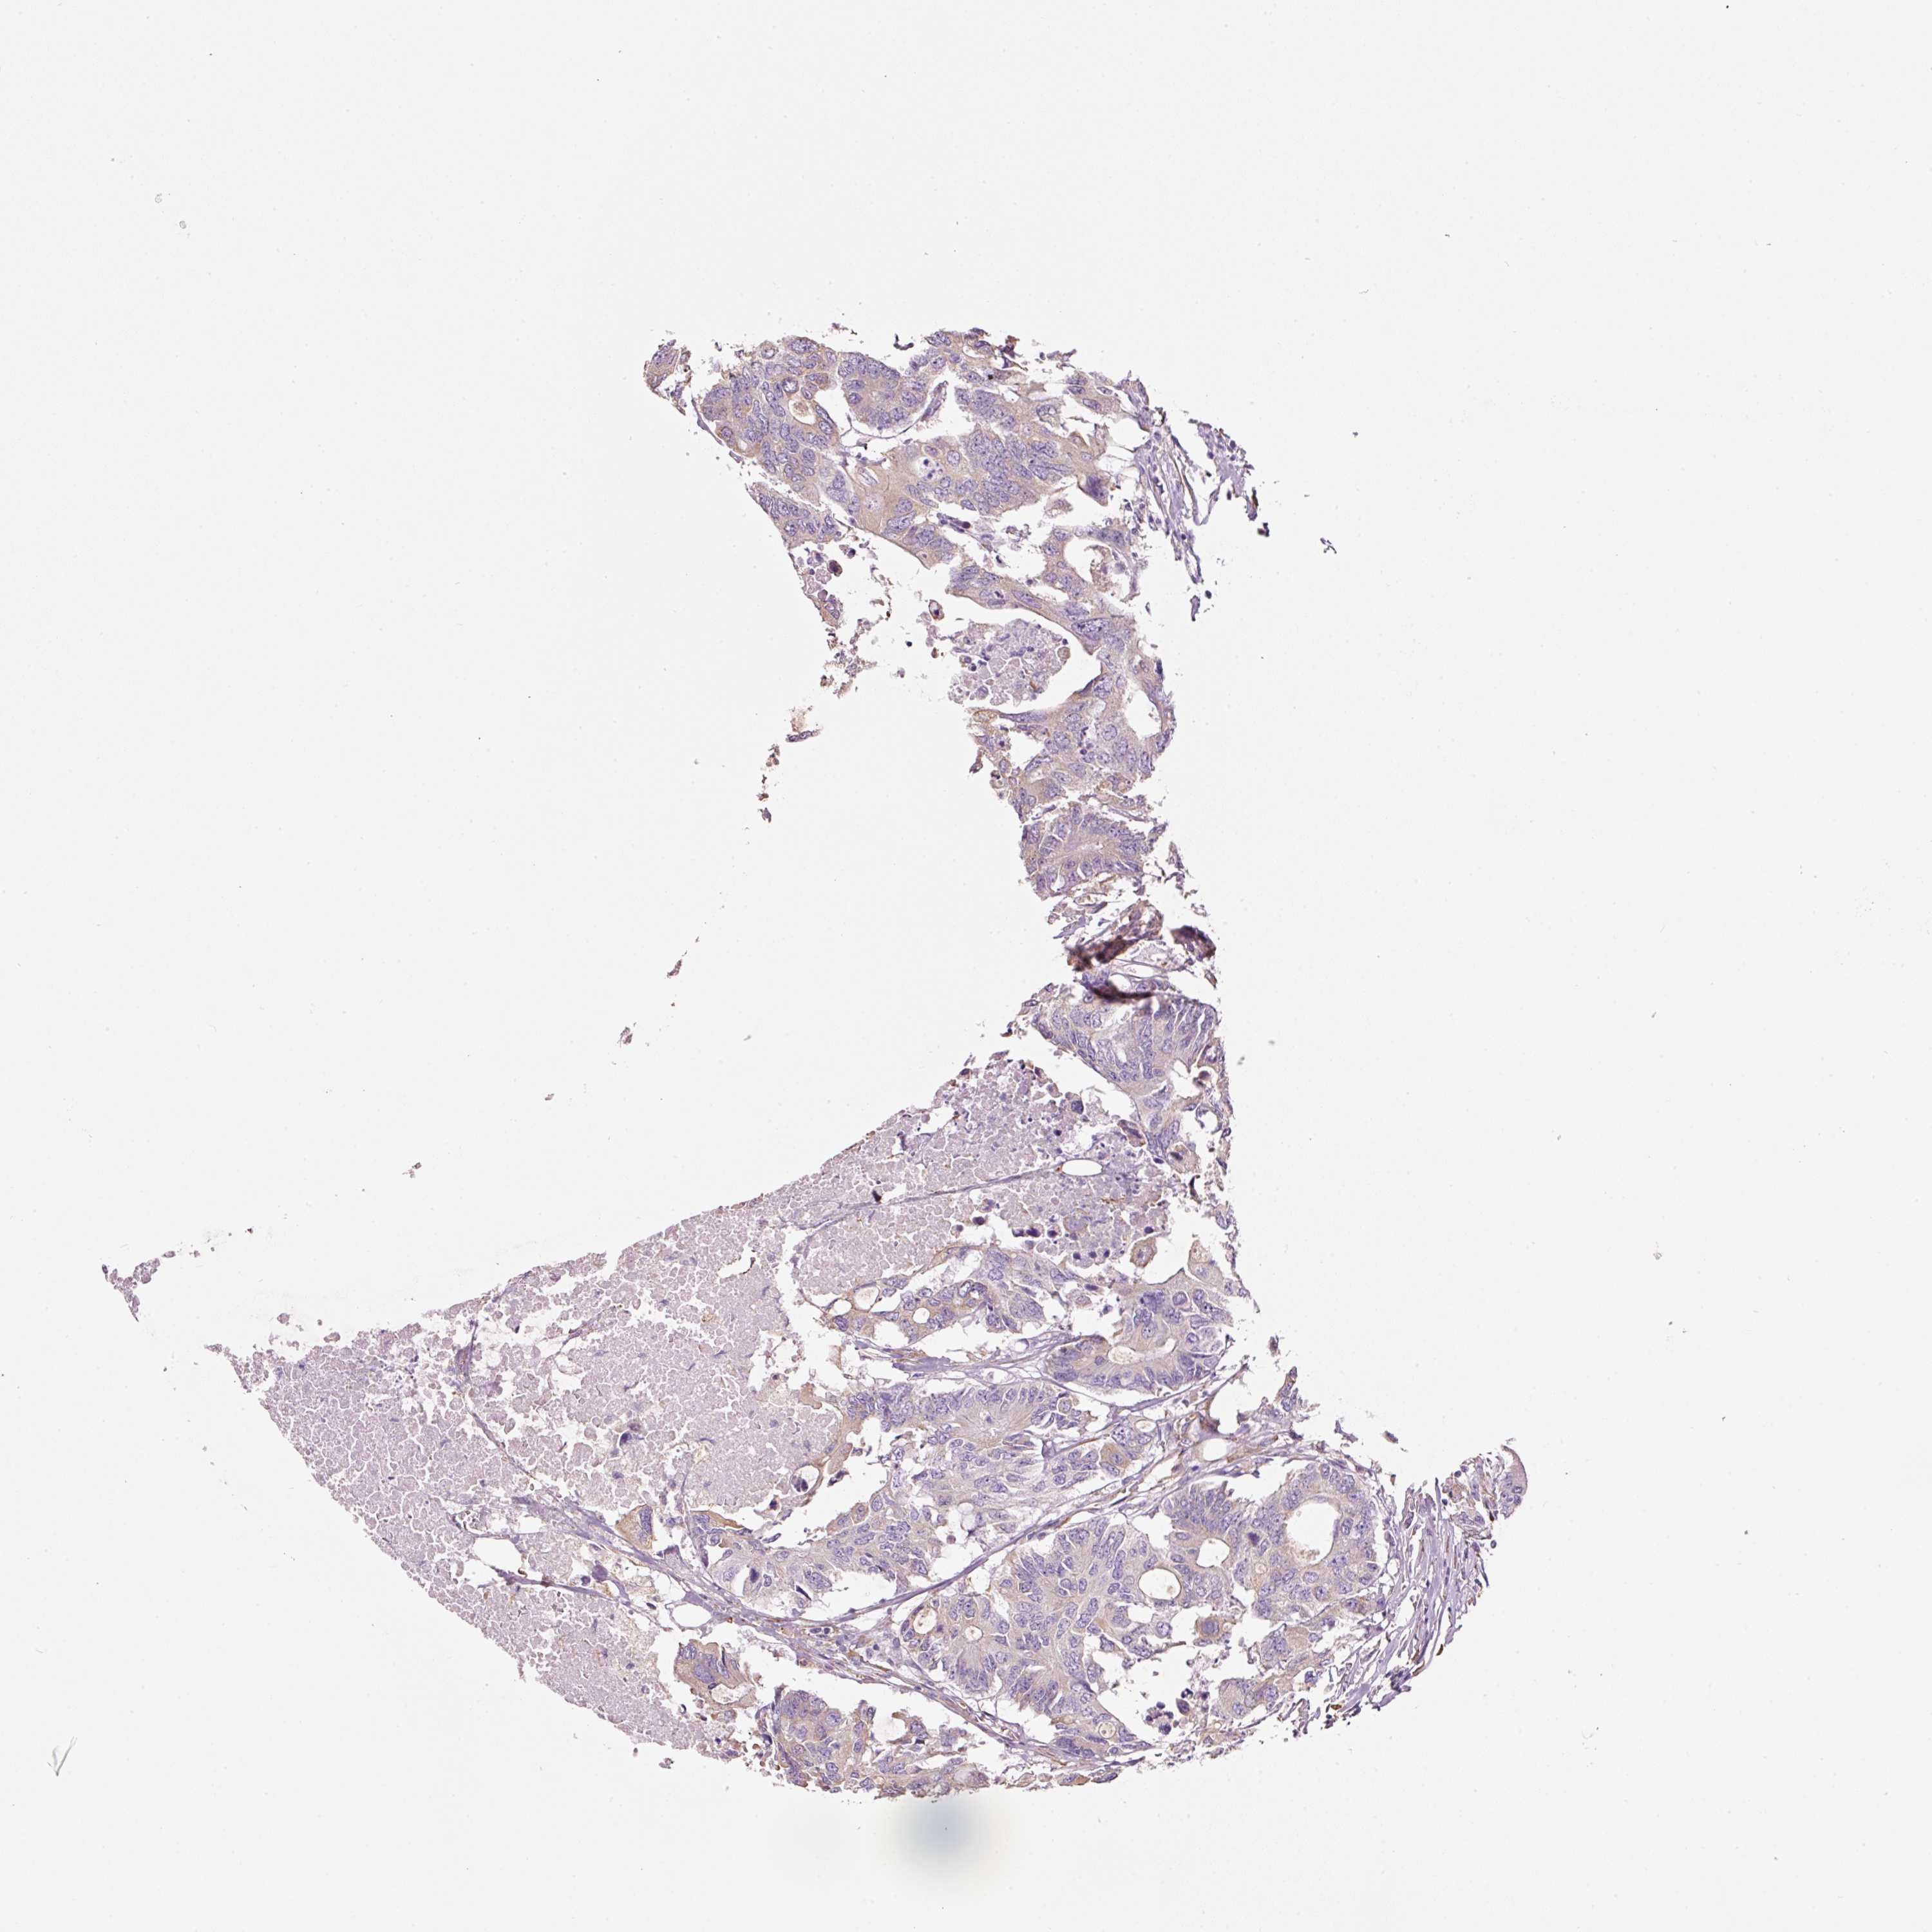

CANCER COLORECTAL CANCER Show tissue menu

Colorectal cancer

Human cancer

Colon adenocarcinoma

Rectum adenocarcinoma